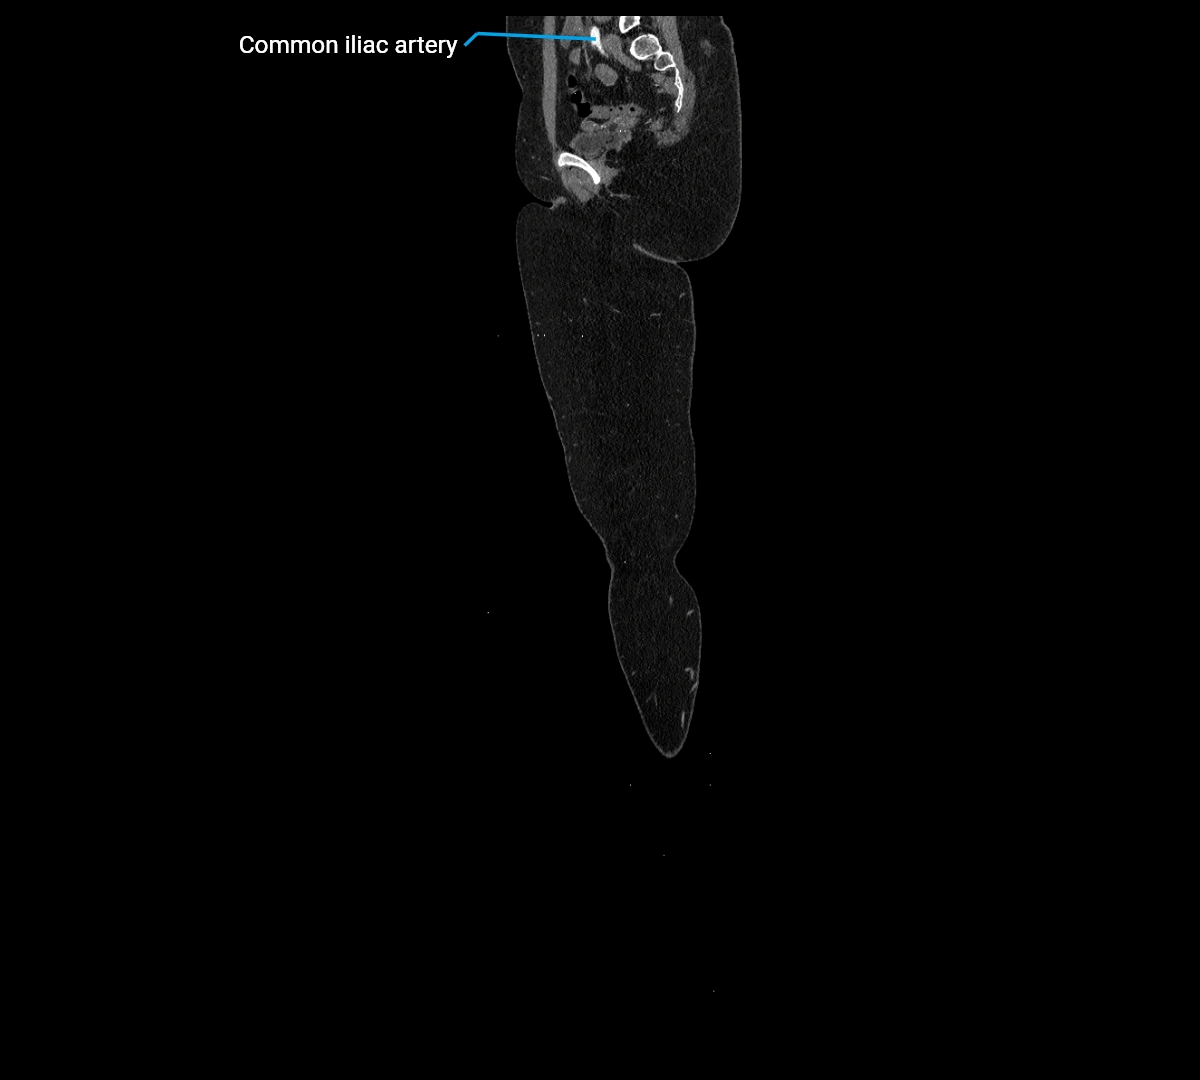

CT images

image

Contrast-enhanced CT (CTA):

• Gold standard for abdominal aortic imaging

• Provides excellent detail of lumen, wall, aneurysm, thrombus, and branch vessels

• Multiplanar and 3D reconstructions help in aneurysm measurement, stent graft planning, and dissection evaluation